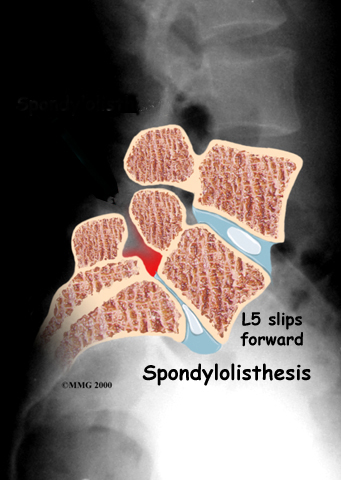

The lumbar spine is made of the lower five vertebrae. Doctors often refer to these vertebrae as L1 to L5. These five vertebrae line up to give the low back a slight inward curve. The of the lumbar spine, L5, connects to the top of the sacrum, a triangular bone at the base of the spine that fits between the two pelvic bones.

Spondylolisthesis from degeneration usually affects people over 50 years old. This condition occurs in African Americans more often than in whites. Women are affected more often than men. The effect of the female hormone estrogen on ligaments and joints is to cause laxity or looseness. The higher levels of estrogen in women may account for the greater incidence of spondylolisthesis. Degenerative spondylolisthesis mainly involves slippage of L4 over L5.

In younger patients (under 20 years old), spondylolisthesis usually involves slippage of the fifth lumbar vertebra over the top of the sacrum. There are several reasons for this. First, the connection of L5 and the sacrum forms an angle that is tilted slightly forward, mainly because the top of the sacrum slopes forward. Second, the slight inward curve of the lumbar spine creates an additional forward tilt where L5 meets the sacrum. Finally, gravity attempts to pull L5 in a forward direction.

Facet joints are small joints that connect the back of the spine together. Normally, the facet joints connecting L5 to the sacrum create a solid buttress to prevent L5 from slipping over the top of the sacrum. However, when problems exist in the disc, facet joints, or bony ring of L5, the buttress becomes ineffective. As a result, the L5 vertebra can slip forward over the top of the sacrum.

Facet joints are small joints that connect the back of the spine together. Normally, the facet joints connecting L5 to the sacrum create a solid buttress to prevent L5 from slipping over the top of the sacrum. However, when problems exist in the disc, facet joints, or bony ring of L5, the buttress becomes ineffective. As a result, the L5 vertebra can slip forward over the top of the sacrum.

A condition called spondylolysis can lead to the slippage that happens with spondylolisthesis. Spondylolysis is a defect in the bony ring of the spinal column. It affects the pars interarticularis, mentioned earlier. This defect is most commonly thought to be a stress fracture that happens from repeated strains on the bony ring. Participants in gymnastics and football commonly suffer these strains. Spondylolysis can lead to the spine slippage when a fracture occurs on both sides of the bony ring. This slippage is called spondylolisthesis. The slippage is from I through IV, one being mild, IV often causing neurological symptoms. The back section of the bony ring separates from the main vertebral body, so the injured vertebra is no longer connected by bone to the one below it. In this situation, the facet joints can't provide their normal support. The vertebra on top is then free to slip forward over the one below.

Facet joints are small joints that connect the back of the spine together. Normally, the facet joints connecting L5 to the sacrum create a solid buttress to prevent L5 from slipping over the top of the sacrum. However, when problems exist in the disc, facet joints, or bony ring of L5, the buttress becomes ineffective. As a result, the L5 vertebra can slip forward over the top of the sacrum.

Facet joints are small joints that connect the back of the spine together. Normally, the facet joints connecting L5 to the sacrum create a solid buttress to prevent L5 from slipping over the top of the sacrum. However, when problems exist in the disc, facet joints, or bony ring of L5, the buttress becomes ineffective. As a result, the L5 vertebra can slip forward over the top of the sacrum.